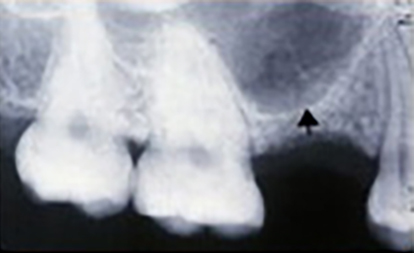

Usually, the sinus lift is done before implant placement because the bone needs a few months to grow, fuse, and become strong. Many studies show that it takes three months for the bone graft to harden and fuse fully.

Since the implant base must sink into the bone, it is best to let the graft set well before placing it.

However, depending on the size of the transplant and the patient’s condition, sinus lift and implant placement may be done simultaneously. Everyone’s situation is different, and the dentist must make decisions.